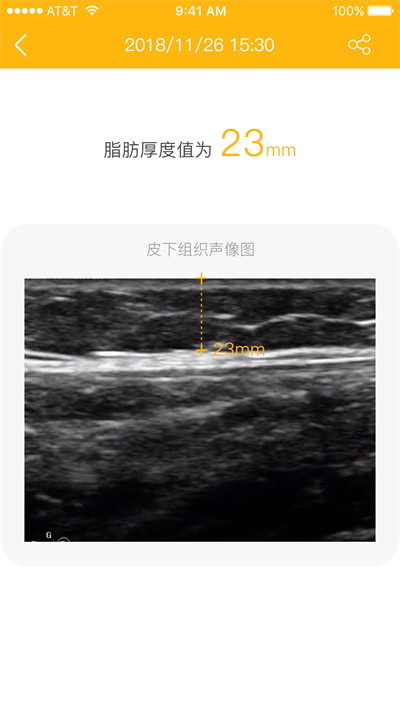

脂肪厚度仪app是一款专为健康管理设计的智能应用,通过与专业测量设备Z1配合使用,为用户提供精准的皮下脂肪监测服务。采用先进的超声波技术,只需简单操作即可快速获取身体多个部位的脂肪厚度数据。无论是健身爱好者、减肥人群还是需要健康监测的用户,都能通过直观的趋势图表和详细的历史记录,轻松掌握身体变化。人性化的分享功能让您能与亲友共同关注健康进展,简洁的界面设计带来流畅的使用体验。

这款创新应用基于超声波原理,能精准测量人体皮下脂肪厚度,特别适合肥胖人群、健身爱好者、爱美女性及糖尿病患者长期监测使用。作为脂肪厚度仪产品Z1的专属配套APP,它不仅提供实时测量功能,还能建立完整的健康档案,让用户全面了解身体脂肪分布情况。通过智能算法分析,帮助用户制定更科学的健康管理计划。

可以测量腰部、上臂、大腿、脸颊、胸部的皮下脂肪厚度;每个部位都提供标准参考值,帮助用户判断测量结果是否在健康范围内。

置于测量处,按下按键,2s输出脂肪厚度数值;智能提示功能确保每次测量位置准确,避免人为误差影响结果。